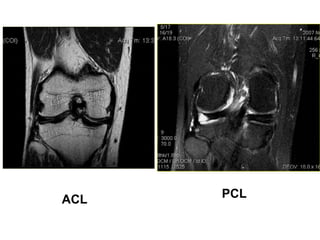

ACL & PCL

ACL PCL

TOÅN THÖÔNG DAÂY CHAÈNG CHEÙO

- Daây chaèng coù höôùng ñi baát thöôøng, maát lieân tuïc moät

phaàn, coù tín hieäu dòch cao treân T2W beân trong, daây

chaèng phuø daøy leân (toån thöông caáp) hay khoâng daøy (toån

thöông maïn).

- Maát lieân tuïc hoaøn toaøn, khoâng thaáy daây chaèng treân

phim.

Toån thöông caáp ACL

TOÅN THÖÔNG DAÂYCHAÈNG CHEÙO - Daây chaèng coù höôùng ñi baát thöôøng, maát lieân tuïc moät phaàn, coù tín hieäu dòch cao treân T2W beân trong, daây chaèng phuø daøy leân (toån thöông caáp) hay khoâng daøy (toån thöông maïn). - Maát lieân tuïc hoaøn toaøn, khoâng thaáy daây chaèng treân phim.